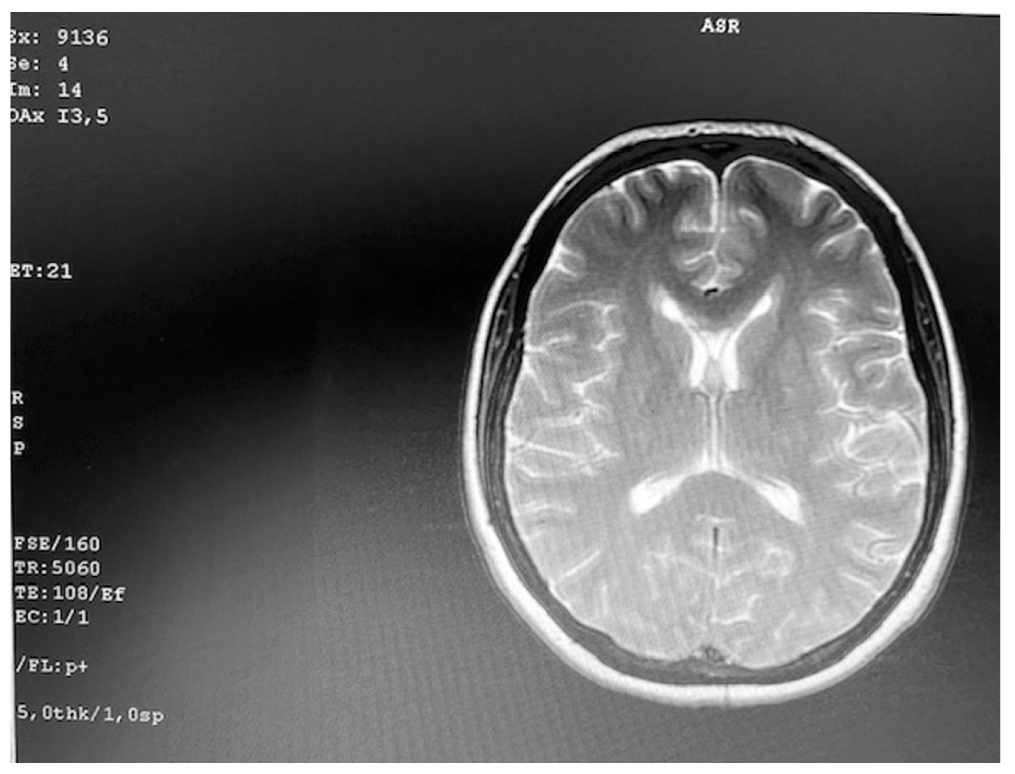

Очаговых изменений со стороны головного мозга по данным неврологического осмотра и МРТ не выявлено (рис. 2).

Рис. 2. МР-картина микроангиопатии. Очаговых изменений со стороны вещества головного мозга не выявлено. / Fig. 2. MR-picture of microangiopathy. Focal changes in the brain substance were not detected.